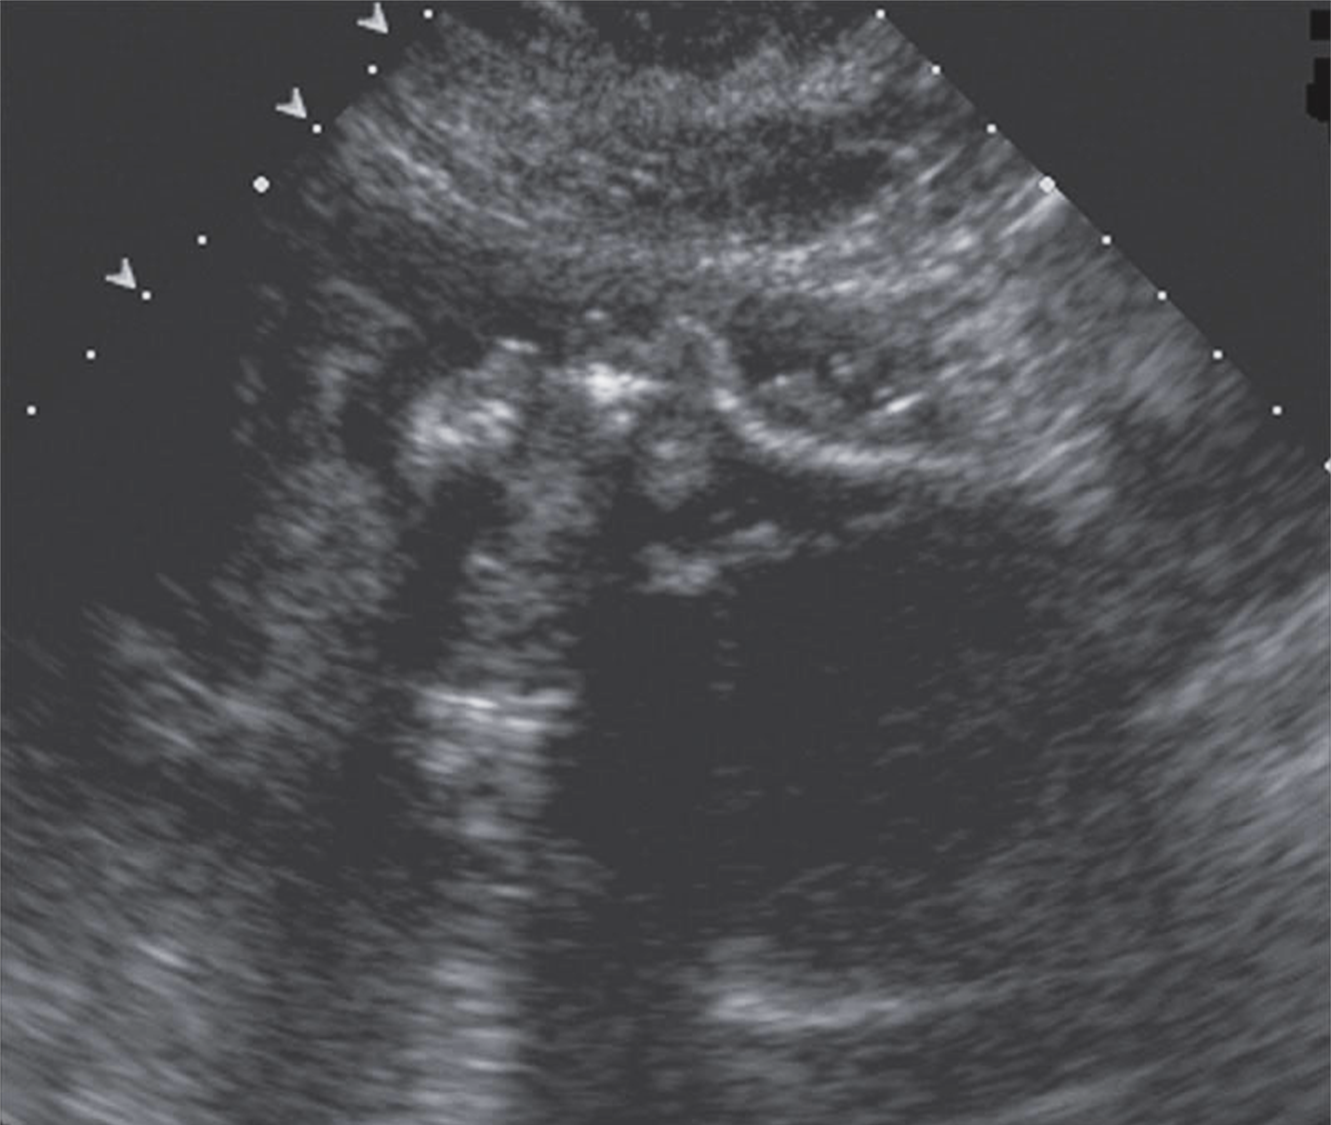

What are these images showing?

Misshaped skulls

What is this image showing?

Trigonocephaly